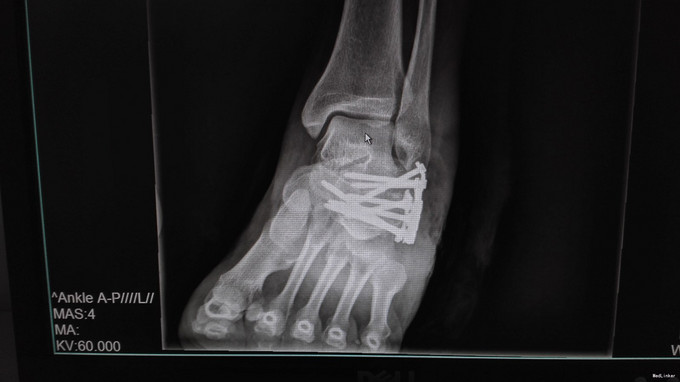

左足跟淤血肿胀明显,无明显畸形,皮肤完整,局部压痛明显,可扪及骨擦感,纵向叩击痛阳性,足趾活动正常,末梢血运、感觉正常。左跟骨X片示:左跟骨粉碎性骨折,左足部CT示:左侧跟骨粉碎性骨折,累及跟距关节面。

左跟骨粉碎性骨折,排除手术禁忌症后行左跟骨粉碎性骨折切开复位内固定术。

中年男性患者,因“跌倒致左足跟部疼痛、活动受限4小时”入院,左跟骨X片及左足部CT提示:左跟骨粉碎性骨折,累及跟距关节面。结合临床症状、体征及影像学检查,诊断左跟骨粉碎性骨折,且累及关节面,手术指征明确,排除手术禁忌后行切开复位内固定术,术后复查X片示对位良好。出院1月后复查,1月内避免负重。